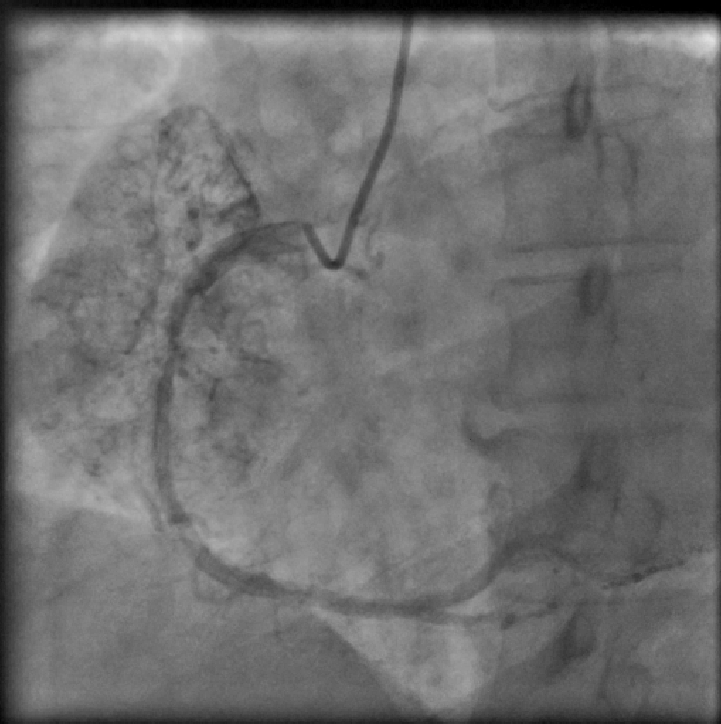

A 39-year-old female patient presented with complaints of retrosternal chest pain and shortness of breath associated with giddiness for the five days preceding the visit. She also complained of weight loss over the past two months. Six months prior, she underwent a coronary angiogram for similar complaints, which revealed normal epicardial coronary arteries with no atherosclerosis and an arteriovenous (AV) fistula in the right coronary artery (RCA). The patient had a history of hypertension and of pulmonary tuberculosis, which was treated medically.